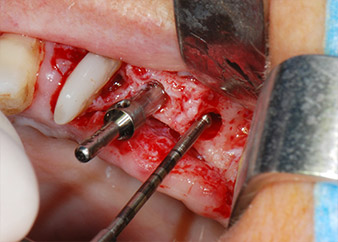

Sinus lift and implant placement

Prior to implant placement, infected tissue was removed from the alveolar bone in the implant site and around the abutment teeth with an insert originally designed for bone shaping and collecting bone chips (Piezomed, insert B5) (Figs. 6 and 7).

implant motor

Fig. 8: Rotary preparation of the implant bed short of the floor of the maxillary sinus at position 25, carried out with an updated implant motor.

Implant beds were prepared at sites 25 and 26 with rotary instruments, used in a contra-angle handpiece with a 20 : 1 transmission ratio with an updated powerful implant motor (Implantmed, W&H) (Fig. 8).

The final preparation next to the sinus was again carried out with a piezoelectric instrument (Piezomed, insert S2).